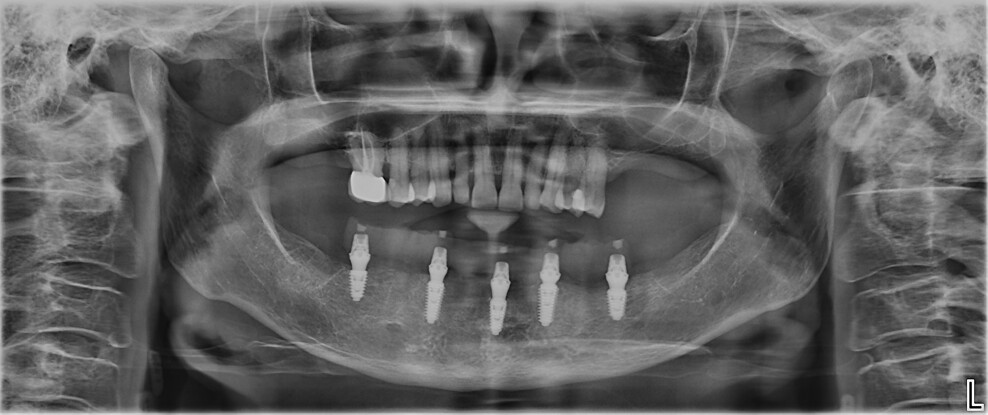

Fig. 9: Panoramic radiograph after five months of healing.

Final prosthetic workflow

After a five-month healing period, fabrication of the definitive restoration was initiated (Figs. 9 & 10). The Medit SmartX workflow was employed, though the scan body matching was performed manually rather than using the software’s automatic feature (Figs. 11a & b). Three intra-oral scans were acquired: a scan of the SmartFlag scan bodies, a scan of the edentulous mandibular ridge and a scan of the provisional restoration in place. These datasets were aligned to replicate the occlusal scheme and soft-tissue contours (Figs. 12a & b; 13a & b).